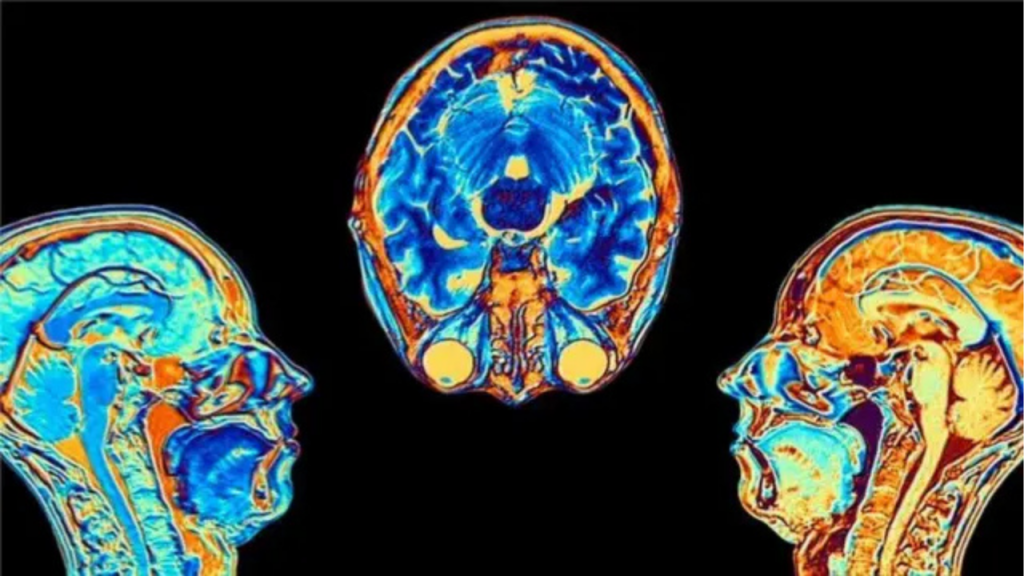

Resonancias magnéticas revelan cambios estructurales y químicos

Un estudio reciente utilizó resonancia magnética multimodal para analizar el cerebro de pacientes con COVID-19 persistente, personas recuperadas sin síntomas y un grupo de control sano. Esta técnica permitió observar tanto la estructura como la química cerebral con gran precisión.

Los resultados mostraron diferencias claras en regiones clave relacionadas con la memoria, la cognición y la función cerebral general. Estas diferencias no solo aparecieron en pacientes con COVID-19 persistente, sino también en personas que no presentaban síntomas posteriores a la infección por el virus.

Uno de los hallazgos más relevantes fue el cambio en la intensidad de la señal de la mielina, una sustancia que protege las neuronas. Este aumento podría representar un proceso de remielinización, es decir, el intento del cerebro de reparar daños causados por la COVID-19.

También se observaron alteraciones en el tronco encefálico, una región esencial para funciones automáticas como la respiración y el ritmo cardíaco. Este hallazgo coincide con otros estudios que vinculan esta zona con síntomas persistentes tras la COVID-19.

Además, los investigadores detectaron desequilibrios metabólicos cerebrales, lo que indica cambios en la actividad química del cerebro. Estos cambios se correlacionaron con la gravedad de los síntomas en algunos pacientes, lo que sugiere una relación directa entre el virus responsable de la COVID-19 y el funcionamiento cerebral.

Estos resultados confirman que el impacto de la COVID-19 puede ser profundo, incluso cuando los síntomas desaparecen.